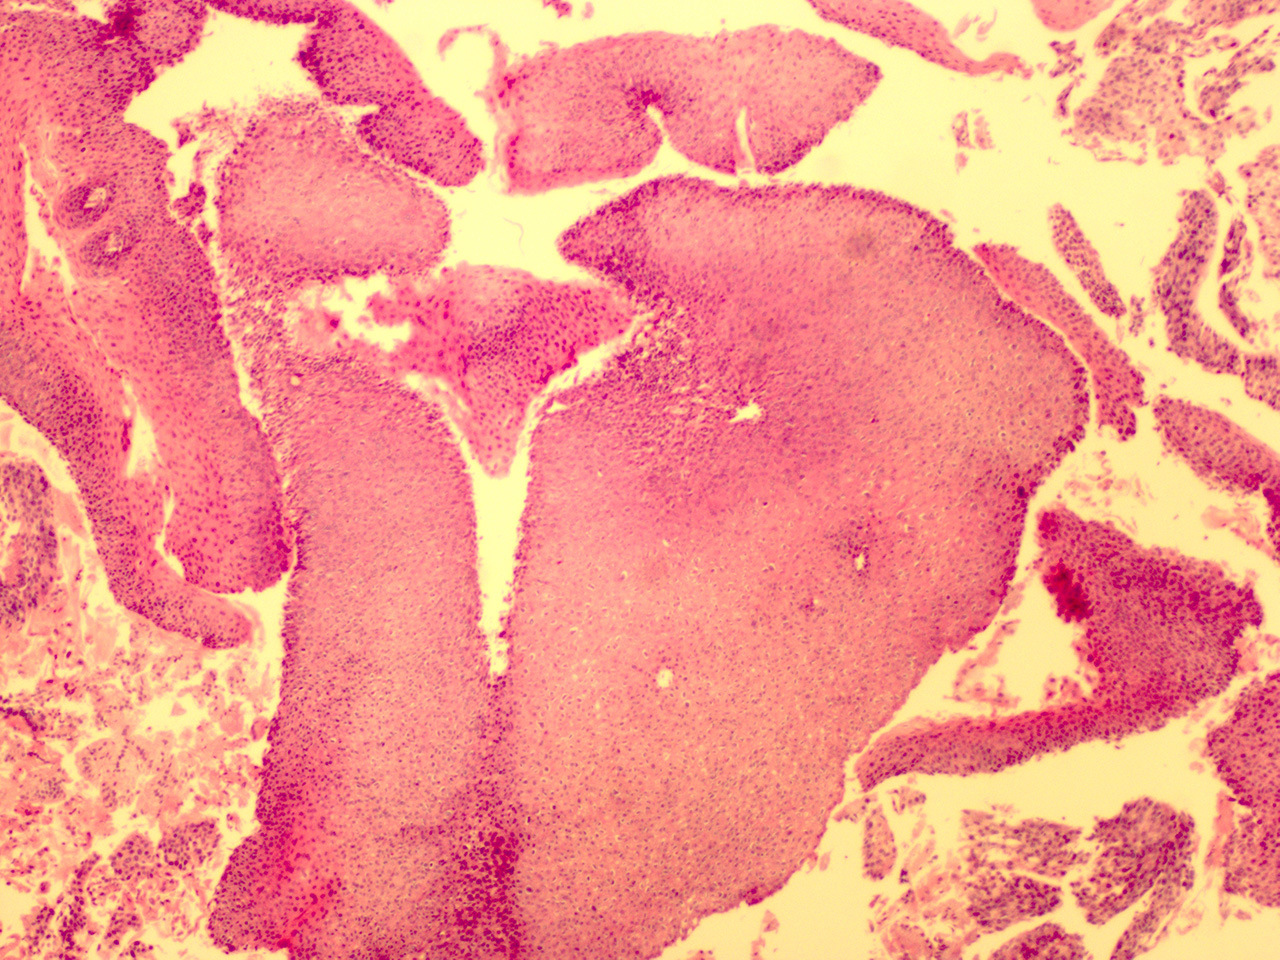

Case 3

Soft Bx CIN 2-3 10x - Low Power